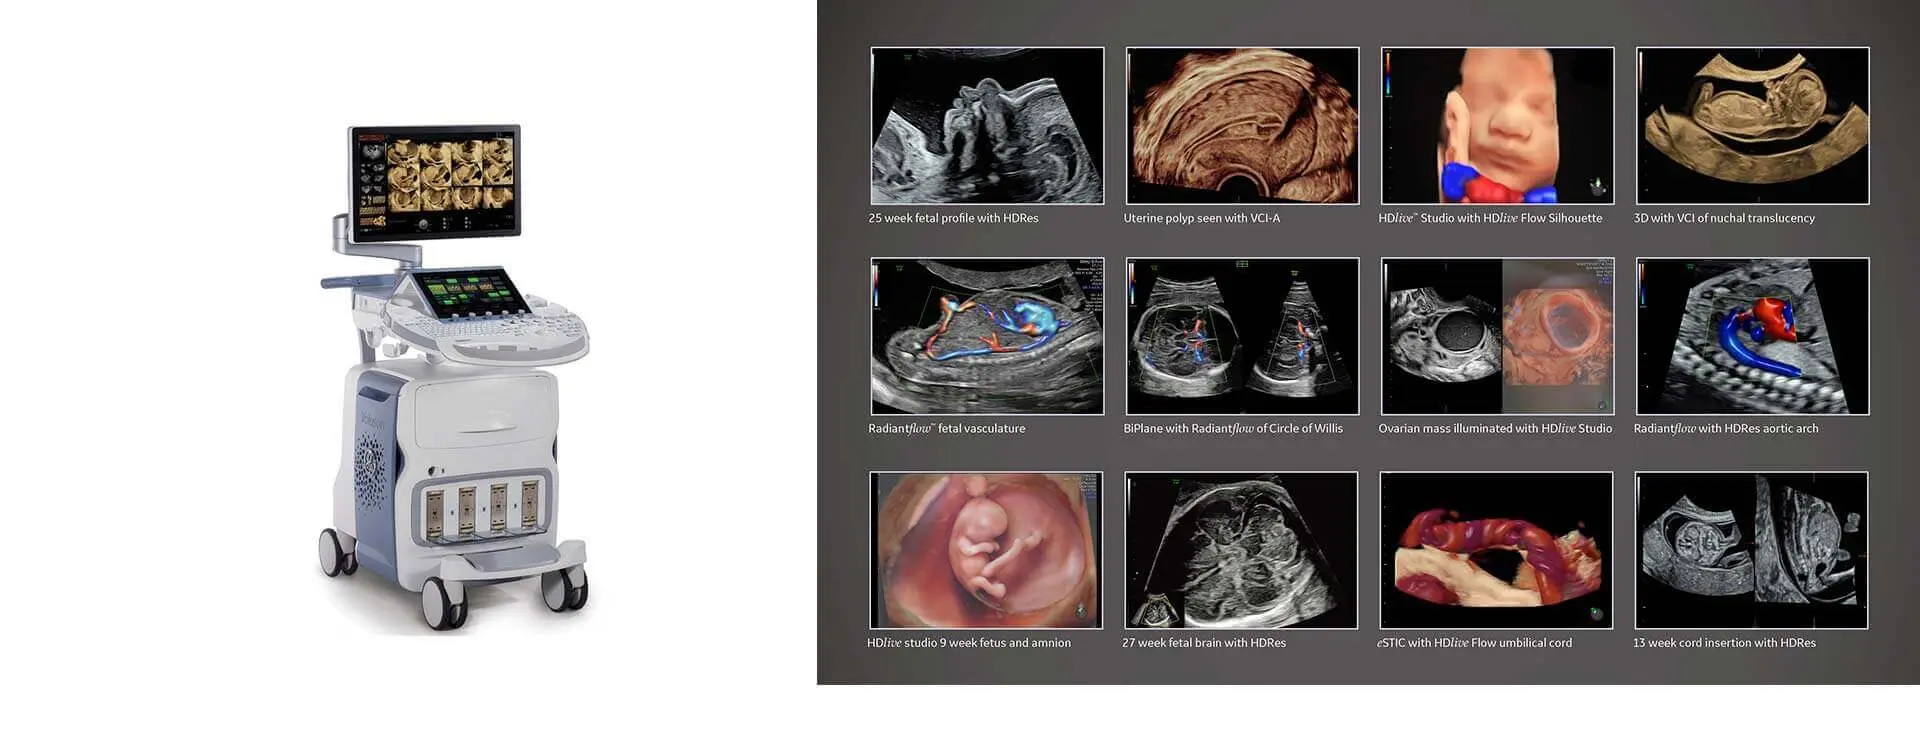

Our Services

We are a large team of radiologists working either on specific modalities

or specialize in organ specific imaging.